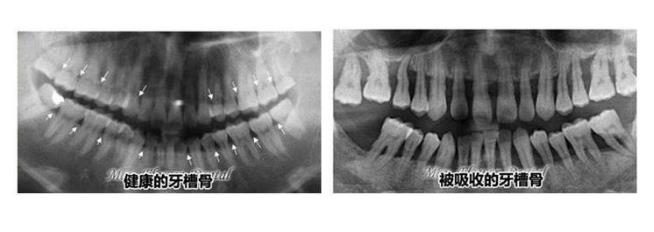

一般牙周炎的主要症狀是:牙齦萎縮、牙槽骨吸收,口臭,甚至是牙齒鬆動、脫落的情況,所以一般出現了牙周炎,需要先洗牙去除口腔內(nei) 的牙結石和牙菌斑,減少對牙齦的刺激。保障口腔的幹淨清爽,然後再做進一步的治療,比如說根麵平整術,消除牙周袋內(nei) 的細菌。